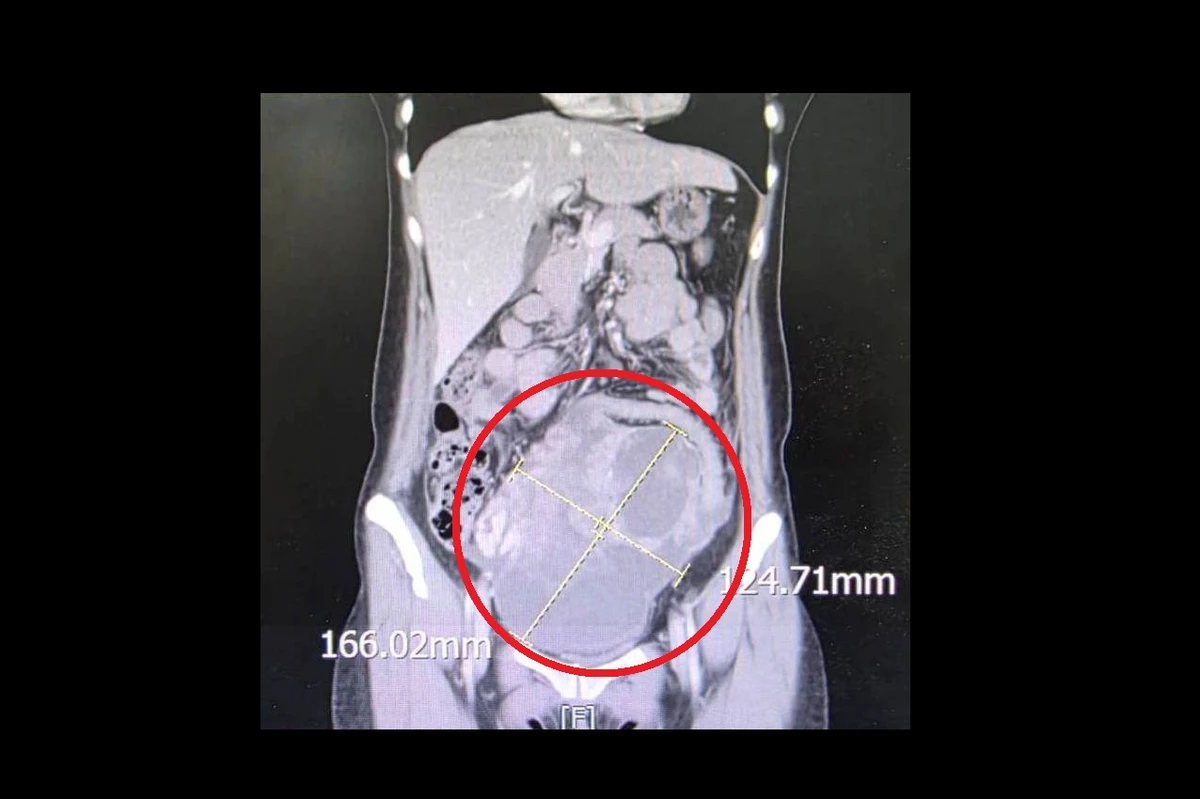

一名44歲未婚女性,持續2週感到腹痛、腹脹且食慾不振,原以為是腸胃不適,就醫檢查後竟在腹部發現直徑16公分的腫瘤,且癌症指數飆升至900單位/毫升。後續,醫院緊急安排手術切除子宮及兩側卵巢,術後病理報告證實為罕見的「同步性子宮內膜癌與卵巢癌」,在醫療團隊悉心治療下,病人至今復原狀況良好。

個案腹痛、腹脹且食慾不振,就醫檢查後竟發現直徑16公分的腫瘤,經診斷為「同步性子宮內膜癌與卵巢癌」。(圖片來源:大千綜合醫院)